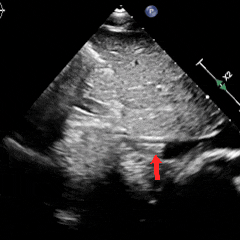

主动脉短轴切面下,封堵器呈Y字型抱住主动脉根部,夹持稳定